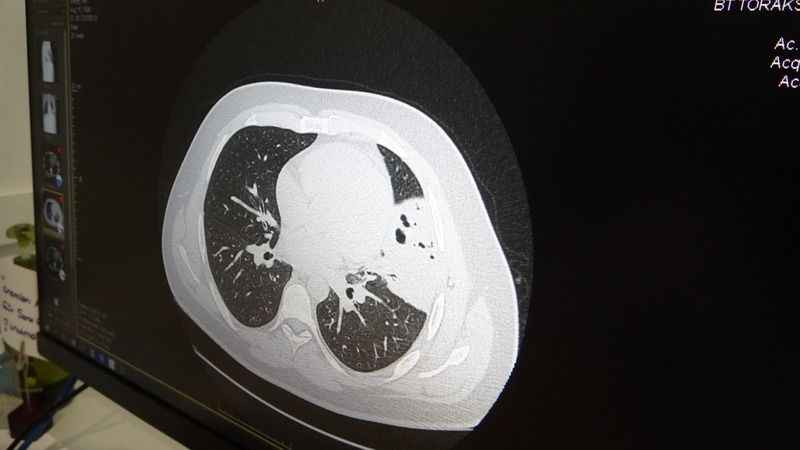

Kronik öksürüklü vakalar da akciğer kökenli bir hastalık olup olmadığı da iyi bir şekilde araştırılması gerektiğini ifade eden Akkaya, "Devam eden kronik öksürüğü olan vakalarda diğer bir sıklıkla karşımıza çıkan sebep de gastroözofageal reflü dediğimiz mide asidinin yemek borusundan yukarıya doğru kaçağıyla ortaya çıkan özellikle boğaz bölgesinin arka tarafında oluşan tahriş sebebiyle kronik öksürük de biraz önce bahsettiğim diğer sebepleriyle ayırıcı tanıda mutlaka düşünülmesi gerekmekte. Basit gribal enfeksiyonların kısa süreli geçişlerinin dışında uzayan öksürük, geniz akıntısı ve burun akıntısı gibi şikayetleri olan vakaların mutlaka en yakın sağlık kurumuna başvurmasını ve iyi bir şekilde evale edilmesini tavsiye ederim” diye konuştu.